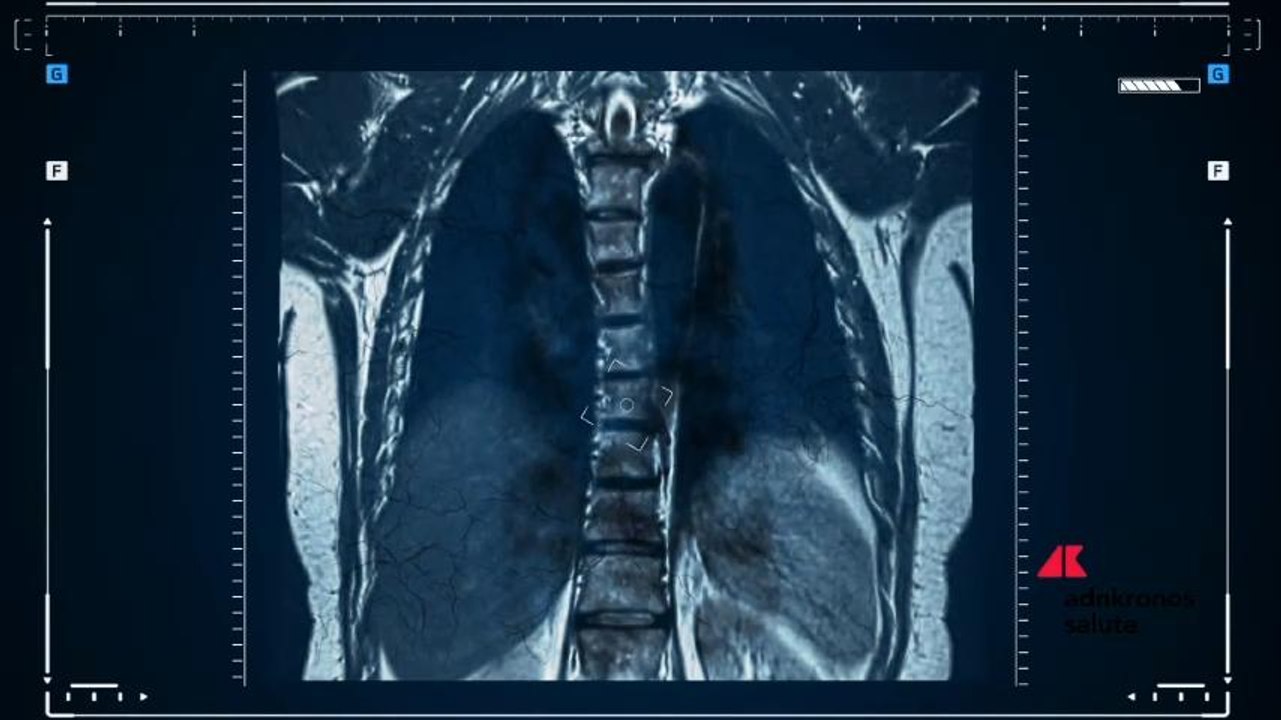

(Adnkronos) - “Nuove tecnologie hanno aperto la strada alla radiomica: un sistema in grado di elaborare diagnosi dal dato numerico. Tali tecniche” si applicano” in particolare “a tutta la parte oncologica, cioè quando il tessuto da normale diventa patologico”, fornendo “diagnosi precoci” e precise. Così Andrea Giovagnoni, presidente nazionale Sirm, Società italiana di radiologia medica e interventistica, nella terza giornata del 51° Congresso Nazionale Sirm, in corso al Mico di Milano, intervenendo sul nuovo ruolo del radiologo in oncologia.